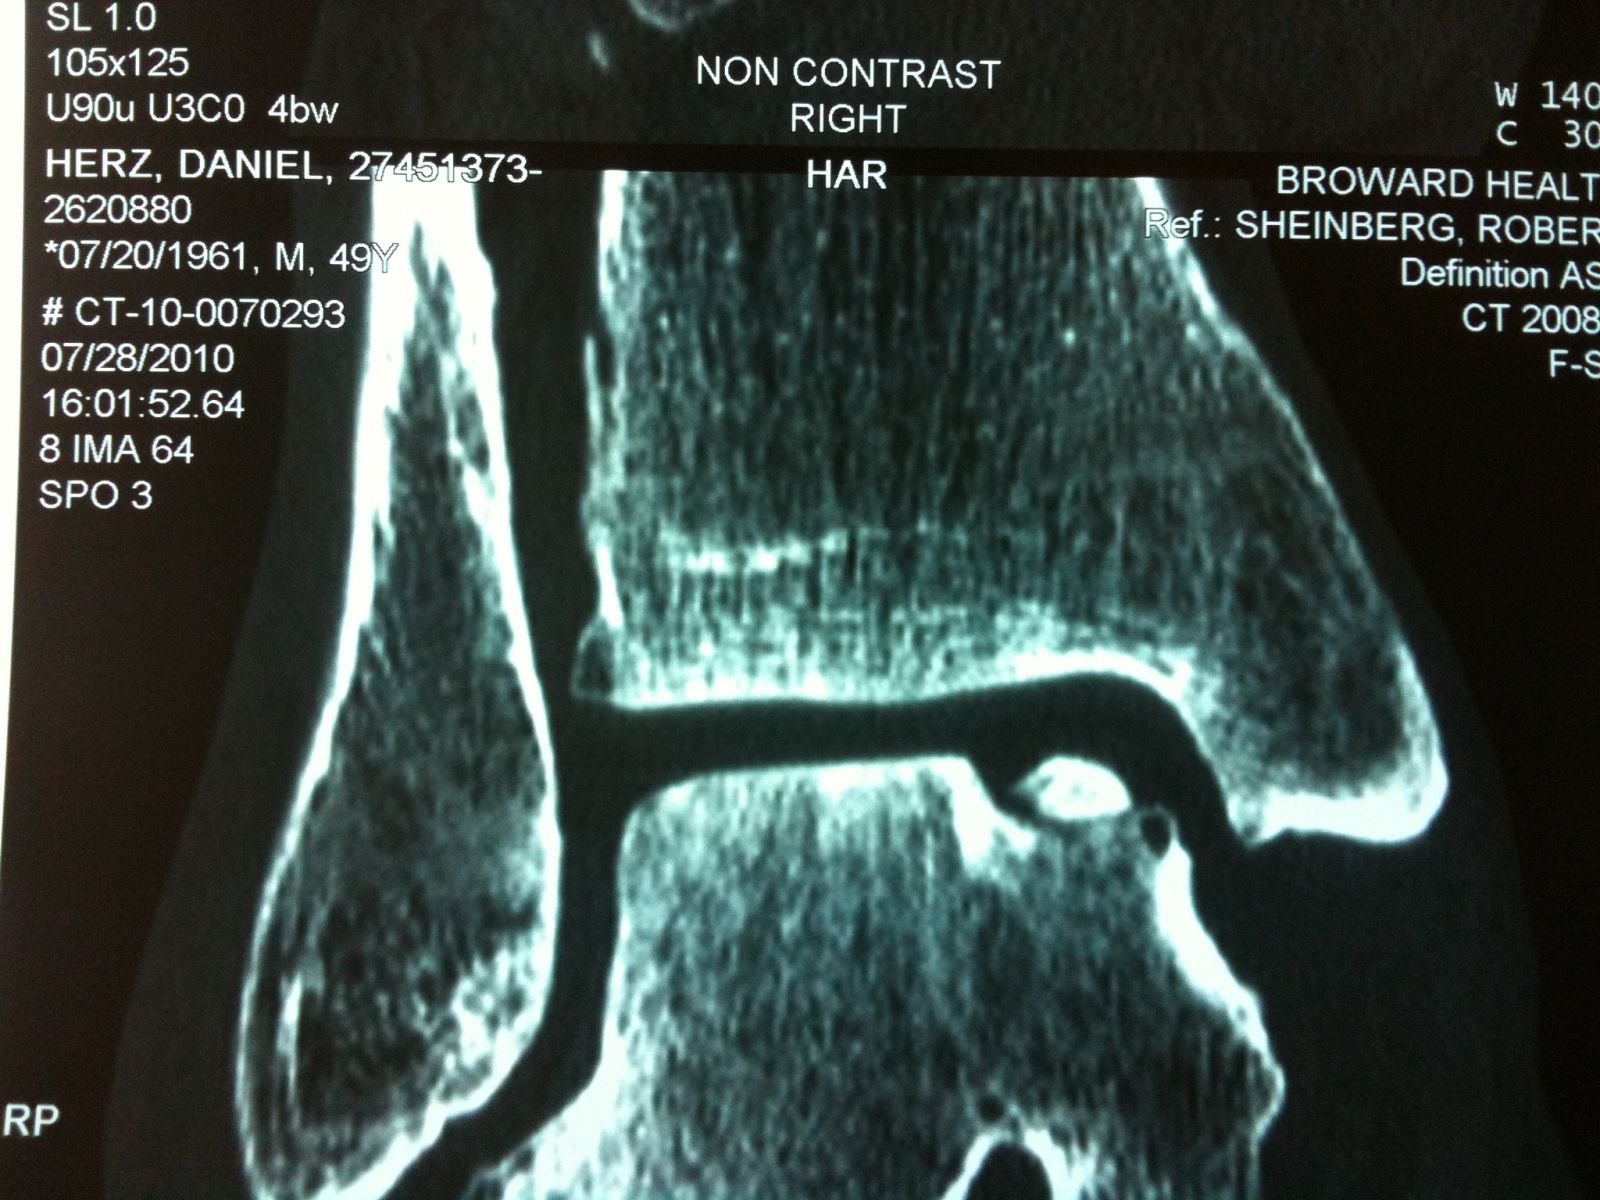

Series of Pics of Microfracture of large OCD of the Talar Dome